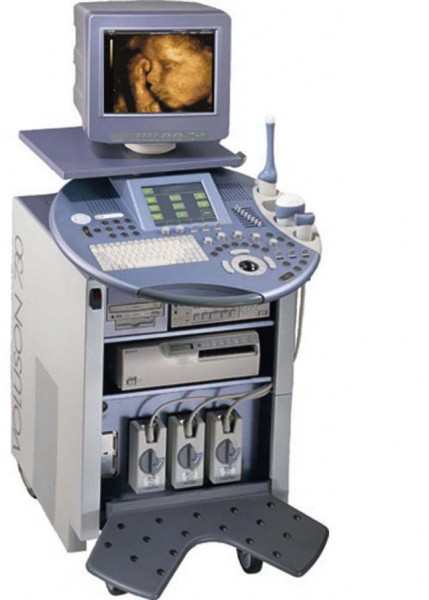

Медицинская Техника: УЗИ с Ge Voluson 730 Expert